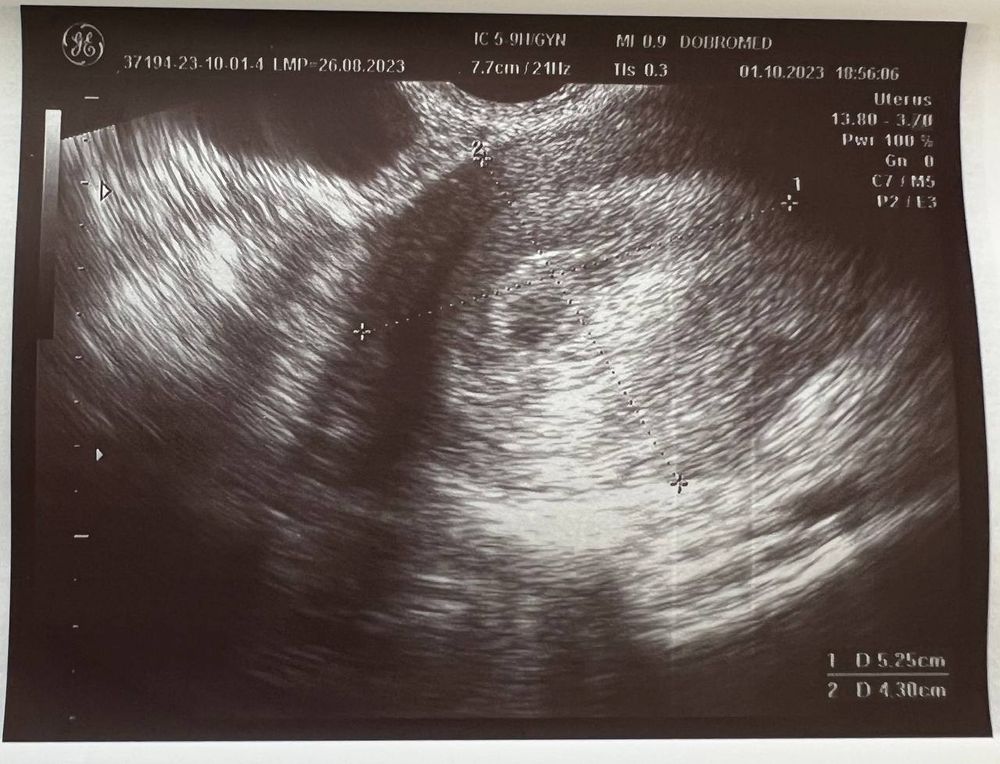

Вчера (1 октября) сходила на УЗИ, беременность подтвердили, маточная.

Размер плодного яйца 4 мм.

Но не видно желтое тело, и мутное содержимое плодного яйца (как она сказала). Меня напугала очень узистка... мол, может быть замершая беременность.

Если есть специалисты тут - пожалуйста, посмотрите снимок

Ниже фото заключения и УЗИ: